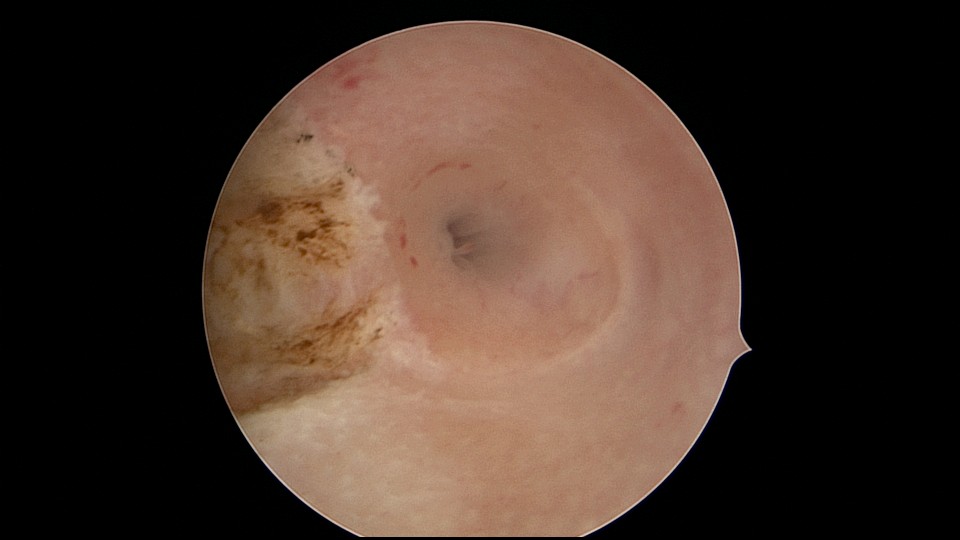

患者21岁,G2P0,两次胎停清宫,月经量减少,眉山某医院B超示宫腔容积小,2021年7月宫腔镜探查,见宫腔两侧、宫底部及左侧宫角粘连,单极电针分粘,恢复宫腔形态,显露双侧输卵管开口。2021年9月宫腔镜二探取球囊,宫腔形态正常,双侧输卵管开口可见。2022年9月自然妊娠12+周,我院建卡,2023年5月孕38+周剖宫产分娩。2025年3月宫腔镜取胚1次,现25岁,G4P1,剖宫产1次。